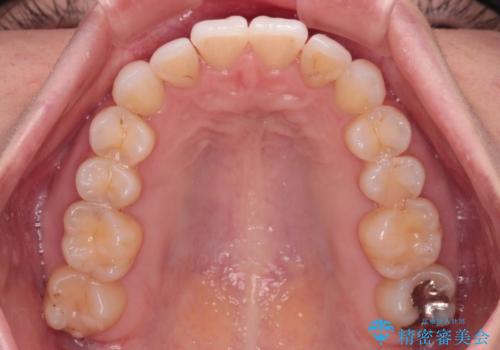

- 上下前歯のデコボコ、特に右上の八重歯を気にして来院された患者様です。

妊娠、出産の予定があり、毎月の通院が困難となる可能性があったため、インビザラインによる矯正治療を行うこととしました。

事前に親知らずを抜歯しておき、出産時期に困ることのないように準備をした上で治療を開始しました。